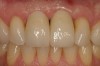

Figure 8  The post-implantation and post-restoration view shows esthetically pleasing, symmetric crowns and mucosal contours, with the Nos. 7 and 10 implant prostheses blending in imperceptibly with the natural dentition. Restoration courtesy of Dr. Jeffrey Warren.

Figure 8